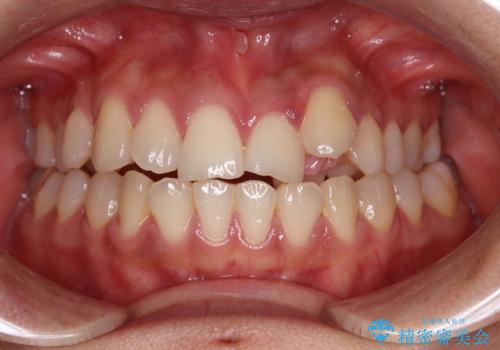

- 左上の前歯のがたつきを主訴に来院された患者様です。

上顎歯列が下顎の歯列に対して狭小であり、一部下顎の奥歯が上顎よりも外側に位置している状態でした。

上顎の歯列を拡大しスペースを設け、さらに左上の小臼歯を一本抜歯し左上の八重歯を歯列内に入れ整えていくことにしました。